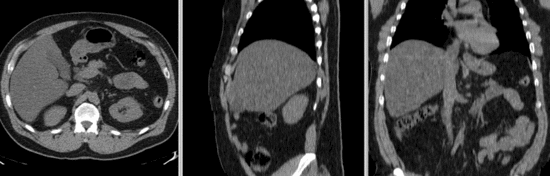

v3.6.1 Slicer3-6Announcement-v1.png Slicer Registration Library Case #08: Intra-subject whole-body PET-CT

• reference/fixed : baseline CT: 0.97 x 0.97 x 3.27 mm , 512 x 512 x 267; PET: 4.7 x 4.7 x 3.3 mm , 128 x 128 x 267

• moving: CT: 0.98 x 0.98 x 5, 512 x 512 x 195; PET: 4.1 x 4.1 x 5 mm, 168 x 168 x 195